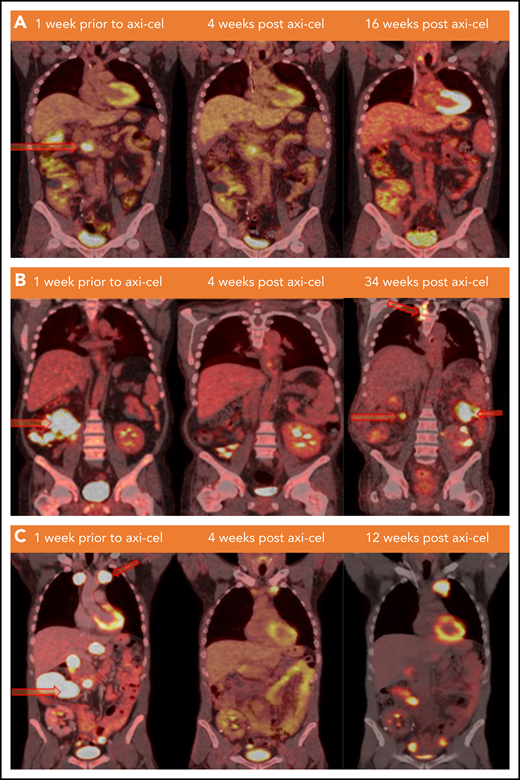

Lymphoma status before and after CAR T-cell infusion. (A) PET/CT scans of patient 1 at the specified time points. Hypermetabolic pancreatic lesion is indicated at week −1 (arrow). (B) PET/CT scans of patient 2 demonstrating from left to right: hypermetabolic cecal mass and ileocolic lymphadenopathy lesions (arrows), no FDG avid lesion (remission), and development of new lesions in thoracic spine, left posterior abdomen, and in the right mid-abdomen (relapse) at weeks −1, +4, and +34 of axi-cel therapy, respectively. (C) PET/CT scan of patient 3 demonstrating from left to right: hypermetabolic left anterior mediastinal mass and multiple abdominal lymph nodes (arrows), interval decreasing in size and metabolic activity of these lesions (partial response), and progression at weeks −1, +4, and +12 of axi-cel therapy, respectively. FDG, fluorodexoglucose.

Patient 1 was a 38-year-old man who underwent kidney transplant for mesalamine-induced nephrotoxicity 10 years before diagnosis of stage IV germinal center B-cell (GCB) DLBCL, was Epstein-Barr virus (EBV)−, and had International Prognostic Index (IPI) score of 3. The disease was refractory to frontline therapy with rituximab, etoposide, prednisone, vincristine, cyclophosphamide, and doxorubicin (R-EPOCH), salvage therapy with gemcitabine, oxaliplatin, and rituximab and subsequently was eligible for axi-cel. Immunosuppressive therapy for kidney transplant consisted of mycophenolate mofetil that was discontinued at the time of DLBCL diagnosis, tacrolimus that was discontinued 2 weeks before leukapheresis, and prednisone that was continued at 5 mg per day. He developed grade 1 CRS on day +6 but did not develop ICANS. Disease assessment with positron emission tomography (PET) scan showed a complete response (CR) at week +4 that was sustained up to week +28 after axi-cel (Figure 1A). The patient remained off immunosuppressive therapy with grossly stable kidney function until week +21 when he had significant rise in serum creatinine. Notably, this was preceded by subclinical evidence of kidney allograft rejection diagnosed at week +16 by a rising dd-cfDNA level from 0.55% to 4.6% and confirmed with a kidney biopsy as borderline cell-mediated rejection (Figure 2). Furthermore, he subsequently developed donor-specific antibodies at week +28, suggesting concurrent antibody-mediated rejection and possibly the loss of functional CAR T-cell persistence because this was associated with a rise in immunoglobulin G (IgG) level (from 650 to 1474 mg/dL; reference range, 610-1616 mg/dL) and CD19 cell count (from 0 to 64 cells per μL) at week +4 after axi-cel and after the diagnosis of graft rejection, respectively. Adequate CAR T-cell expansion was observed within the first 30 days after infusion (Figure 3). However, blood samples were unavailable to assess persistence beyond day +30. His lymphoma remained in remission while renal function declined gradually. At this point, it might have been reasonable to restart the immunosuppression therapy to salvage the graft; however, taking into consideration the lack of prior data estimating the risk of disease relapse with restarting calcineurin inhibitors and weighing the refractory nature of his disease before response with axi-cel therapy, the treating team and patient had an extensive discussion, and the shared decision was to avoid restarting immunosuppressive therapy to minimize potential risk of disease relapse.

Patient 2 was a 44-year-old man who underwent kidney transplant for Alport syndrome 10 years before diagnosis of stage IV GCB-DLBCL, was EBV−, and had an IPI score of 3. The DLBCL was refractory to rituximab, cyclophosphamide, doxorubicin, prednisone, and vincristine after 2 cycles, at which point he was eligible to receive axi-cel on a clinical trial (#NCT03761056). Immunosuppressive therapy for kidney transplant consisted of sirolimus that was discontinued 4 weeks before leukapheresis and prednisone 30 mg per day that was reduced to 4.5 mg/day and then discontinued at weeks −4 and +1 of leukapheresis, respectively. He developed grade 1 CRS with fever on day +5 and grade 3 ICANS on day +8 that was treated with intravenous dexamethasone for 6 days with subsequent resolution by day +13. Six weeks after axi-cel infusion, the patient was hospitalized for treatment of nosocomial pneumonia, and he had acute kidney injury on the day of admission attributed to hypovolemia, which recovered with intravenous fluid within 24 hours. A PET scan on day +30 revealed complete response that was sustained for more than 12 weeks and was associated with hypogammaglobinemia and B-cell aplasia (IgG levels of 319, 247, and 399 mg/dL and undetectable periphral blood CD19+ cells at weeks +4, +8, and +12 of axi-cel infusion, respectively). However, his disease relapsed at +34 weeks, at which point he was treated with radiation plus hyperfractionated cyclophosphamide. CAR-T persistence, CD19+ cells, and IgG were not measured after relapse. Kidney function remained stable at week +36, with <1% dd-cfDNA. He remained off immunosuppressive medications except prednisone 5 mg/day, which was restarted as maintenance therapy at week 8.

Patient 3 was a 41-year-old man with a history of kidney transplant for treatment of granulomatous polyangiitis 7 years prior to diagnosis of stage IV GCB-DLBCL, was EBV−, and had an IPI of 2. The lymphoma was refractory to frontline therapy with R-EPOCH and multiple salvage regimens including rituximab, gemcitabine, dexamethasone, and cisplatin; rituximab, etoposide, methylprednisolone, cytarabine, and cisplatin; and polatuzumab vedotin, bendamustine, and rituximab. Immunosuppressive therapy for kidney transplant consisted of sirolimus that was discontinued 2.5 weeks before leukapheresis and prednisone that was continued at 5 mg/day. No CRS or ICANS was observed after axi-cel therapy. At week +4, a PET scan revealed partial response; however, he developed progressive disease at week +12 despite detectable CAR+ cells in the peripheral blood (4397 CAR copies per µg DNA at week 15) and ongoing B-cell aplasia (undetectable CD19+ cells at weeks +4 and +19 after axi-cel). His kidney function remained stable, and dd-cfDNA levels were <1%. PET-computed tomography scan results and serum creatinine values for patients 1 to 3 are summarized in Figures 1 and 2, respectively.